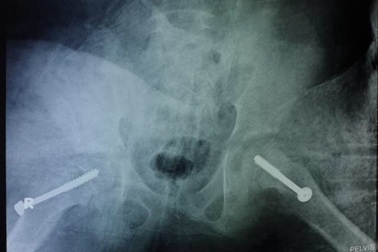

Bé trai trượt chỏm xương đùi cả 2 bên khi chơi đá bóngBị té khi đang chơi đá bóng, cậu bé 11 tuổi bị sưng, đau cả 2 chân, tình trạng ngày càng trở nặng. Các bác sĩ xác định, bệnh nhi bị trượt chỏm xương đùi cả 2 bên nguy cơ hoại tử.